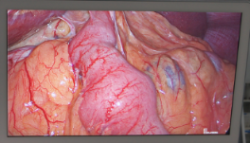

El Hospital La Luz de Madrid se adapta a las nuevas tecnologías y el servicio de Cirugía General y del Aparato Digestivo acaba de incorporar la nueva torre laparoscópica de última generación, IMAGE1 S con tecnología fluorescencia con verde indocianina, mejorando la seguridad y calidad de las intervenciones quirúrgicas.

Este sistema permite al cirujano iluminar homogéneamente la imagen endoscópica (colores brillantes, mejorada percepción de la profundidad), así como aumentar el contraste dinámicamente. Además de disponer de monitores de alta resolución que mejoran la calidad de imagen y la precisión de la intervención, la alteración cromática permite intensificar la diferenciación entre los distintos tipos de tejido.

El verde de indocianina es un colorante de cianina que al inyectarlo en sangre se distribuye por todo el torrente sanguíneo, "el uso de cámaras y ópticas especializadas nos permiten ver toda la distribución vascular de los órganos que tratamos y asegurarnos que los tejidos sanos que dejamos, mantienen buena vascularización y están en óptimas condiciones evitando lesiones por isquemia (falta de vascularización del tejido)", explica el doctor Carlos Durán, jefe de servicio de Cirugía General y del Aparato Digestivo del Hospital La Luz.

Tal y como afirma este especialista, el uso del verde indocianina ofrece múltiples posibilidades para la cirugía hepática, tanto abierta como laparoscópica, "nos facilita la localización de lesiones metastásicas y tumores hepáticos y al finalizar una resección o hepatectomía por tumor, comprobamos la buena vascularización del parénquima hepático residual (el que se deja sano después de resecar). Así mismo detecta las fugas biliares, pues el verde del colorante se elimina por la bilis".

Imagen en alta resolución. Este enlace se abrirá mediante lightbox, puede haber un cambio de contextoEn el Hospital La Luz, el abordaje combinado del cáncer de esófago por vía laparoscópica y toracoscópica es ya una rutina y se realiza en la práctica totalidad de los casos. "El punto más conflictivo de la cirugía esofágica, es asegurar la buena vascularización de la porción de estómago con el que se confecciona la plastia esofágica (el nuevo esófago), pues esta es la causa de la mayor parte de las fistulas a nivel de anastomosis (unión) entre el esófago sano y el estómago ascendido (nuevo esófago,) siendo además una complicación grave y de difícil manejo. Con este nuevo sistema y el uso de la fluorescencia con verde indocianina, nos asegura que el nuevo estómago que ascendemos está perfectamente vascularizado, lo cual minimiza la incidencia de fallos a nivel de la sutura entre el esófago y el estómago y acorta los periodos de estancia hospitalaria", asevera Carlos Durán.